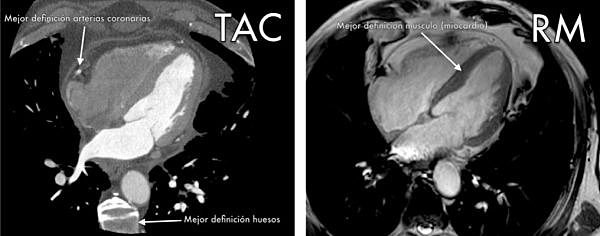

• Imágenes RM está sustentada en la de la tomografía computada

Imágenes RM está sustentada en la de la tomografía computada

En este punto es importante recordar que la reconstrucción de imágenes RM está sustentada en la de la tomografía computada, es decir en el trabajo fecundo de Johan Radon quien en 1917 demostró la posibilidad de reconstrucción tridimensional de un objeto a partir de un juego infinito de sus proyecciones y de Allan M. Cormack (premio Nobel 1979 por la tomografía computada), quien resolvió en 1963 y 1964, el problema de conocer el interior de una región a partir de conocer sus proyecciones